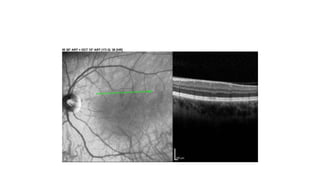

Normal Anatomy

ILM, RNFL, OPL,IPL Hyper Reflective

GCL, INL,ONL Hypo Reflective